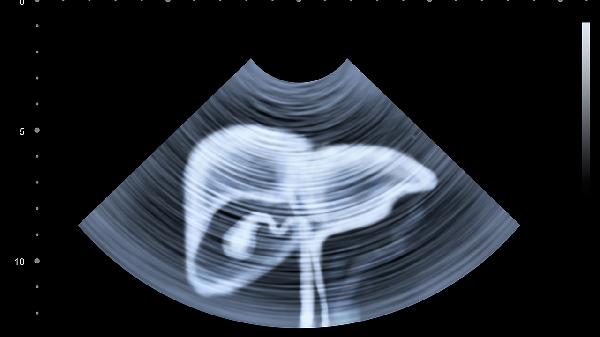

肝脏超声利用声波成像观察肝脏形态、大小及血流情况,对囊肿、血管瘤等占位性病变的初步筛查效果显著。该检查无辐射且操作简便,但对操作者经验依赖较大,对于小于1厘米的病灶可能漏诊。适用于常规体检和肝硬化患者的长期随访。